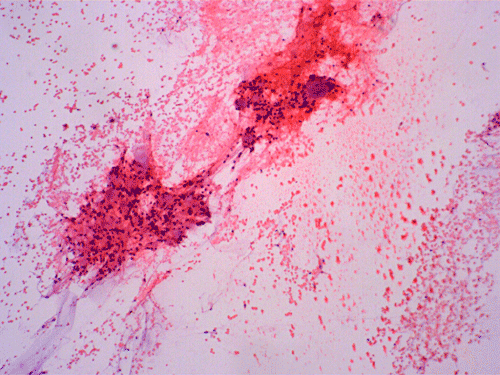

On cytologic preparations, there are clumps of tissue that do not smear out well (Panel A). On higher magnification, these tissue clusters are composed of large blobs of bluish, acellular, mucoid material admixed with cells with relatively uniform, bland nuclei and small amount of cytoplasm (Panel B). In the less tightly packed areas, the long cytoplasmic processes of the cells can be well appreciated (Panel C). These long processes are highly suggestive of a glial neoplasm. On frozen sections, the lesion is composed of multiple blobs of bluish, mucoid material surrounded by tumor cells (Panel D and E). Features of the paraffin sections are not that much different from that of the frozen sections (Panel F G H).